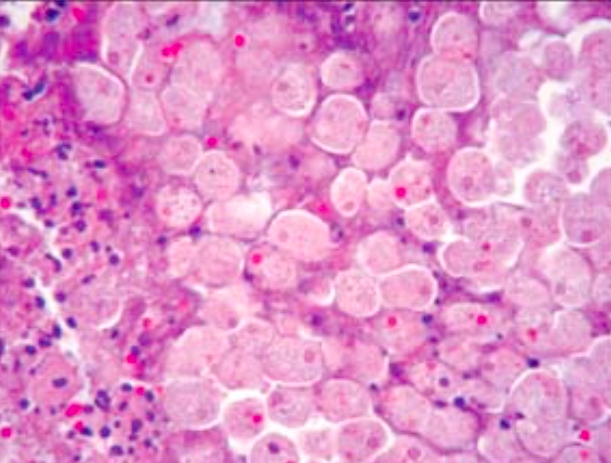

What are these cells from in an unvaccinated child that presents with a maculopapular rash and pneumonia?

Measles infects epithelial cells of the upper respiratory tract and promotes giant cell formation. Note the eosinophilic inclusions in the nucleus and cytoplasm (Warthin-Finkeldey cells).